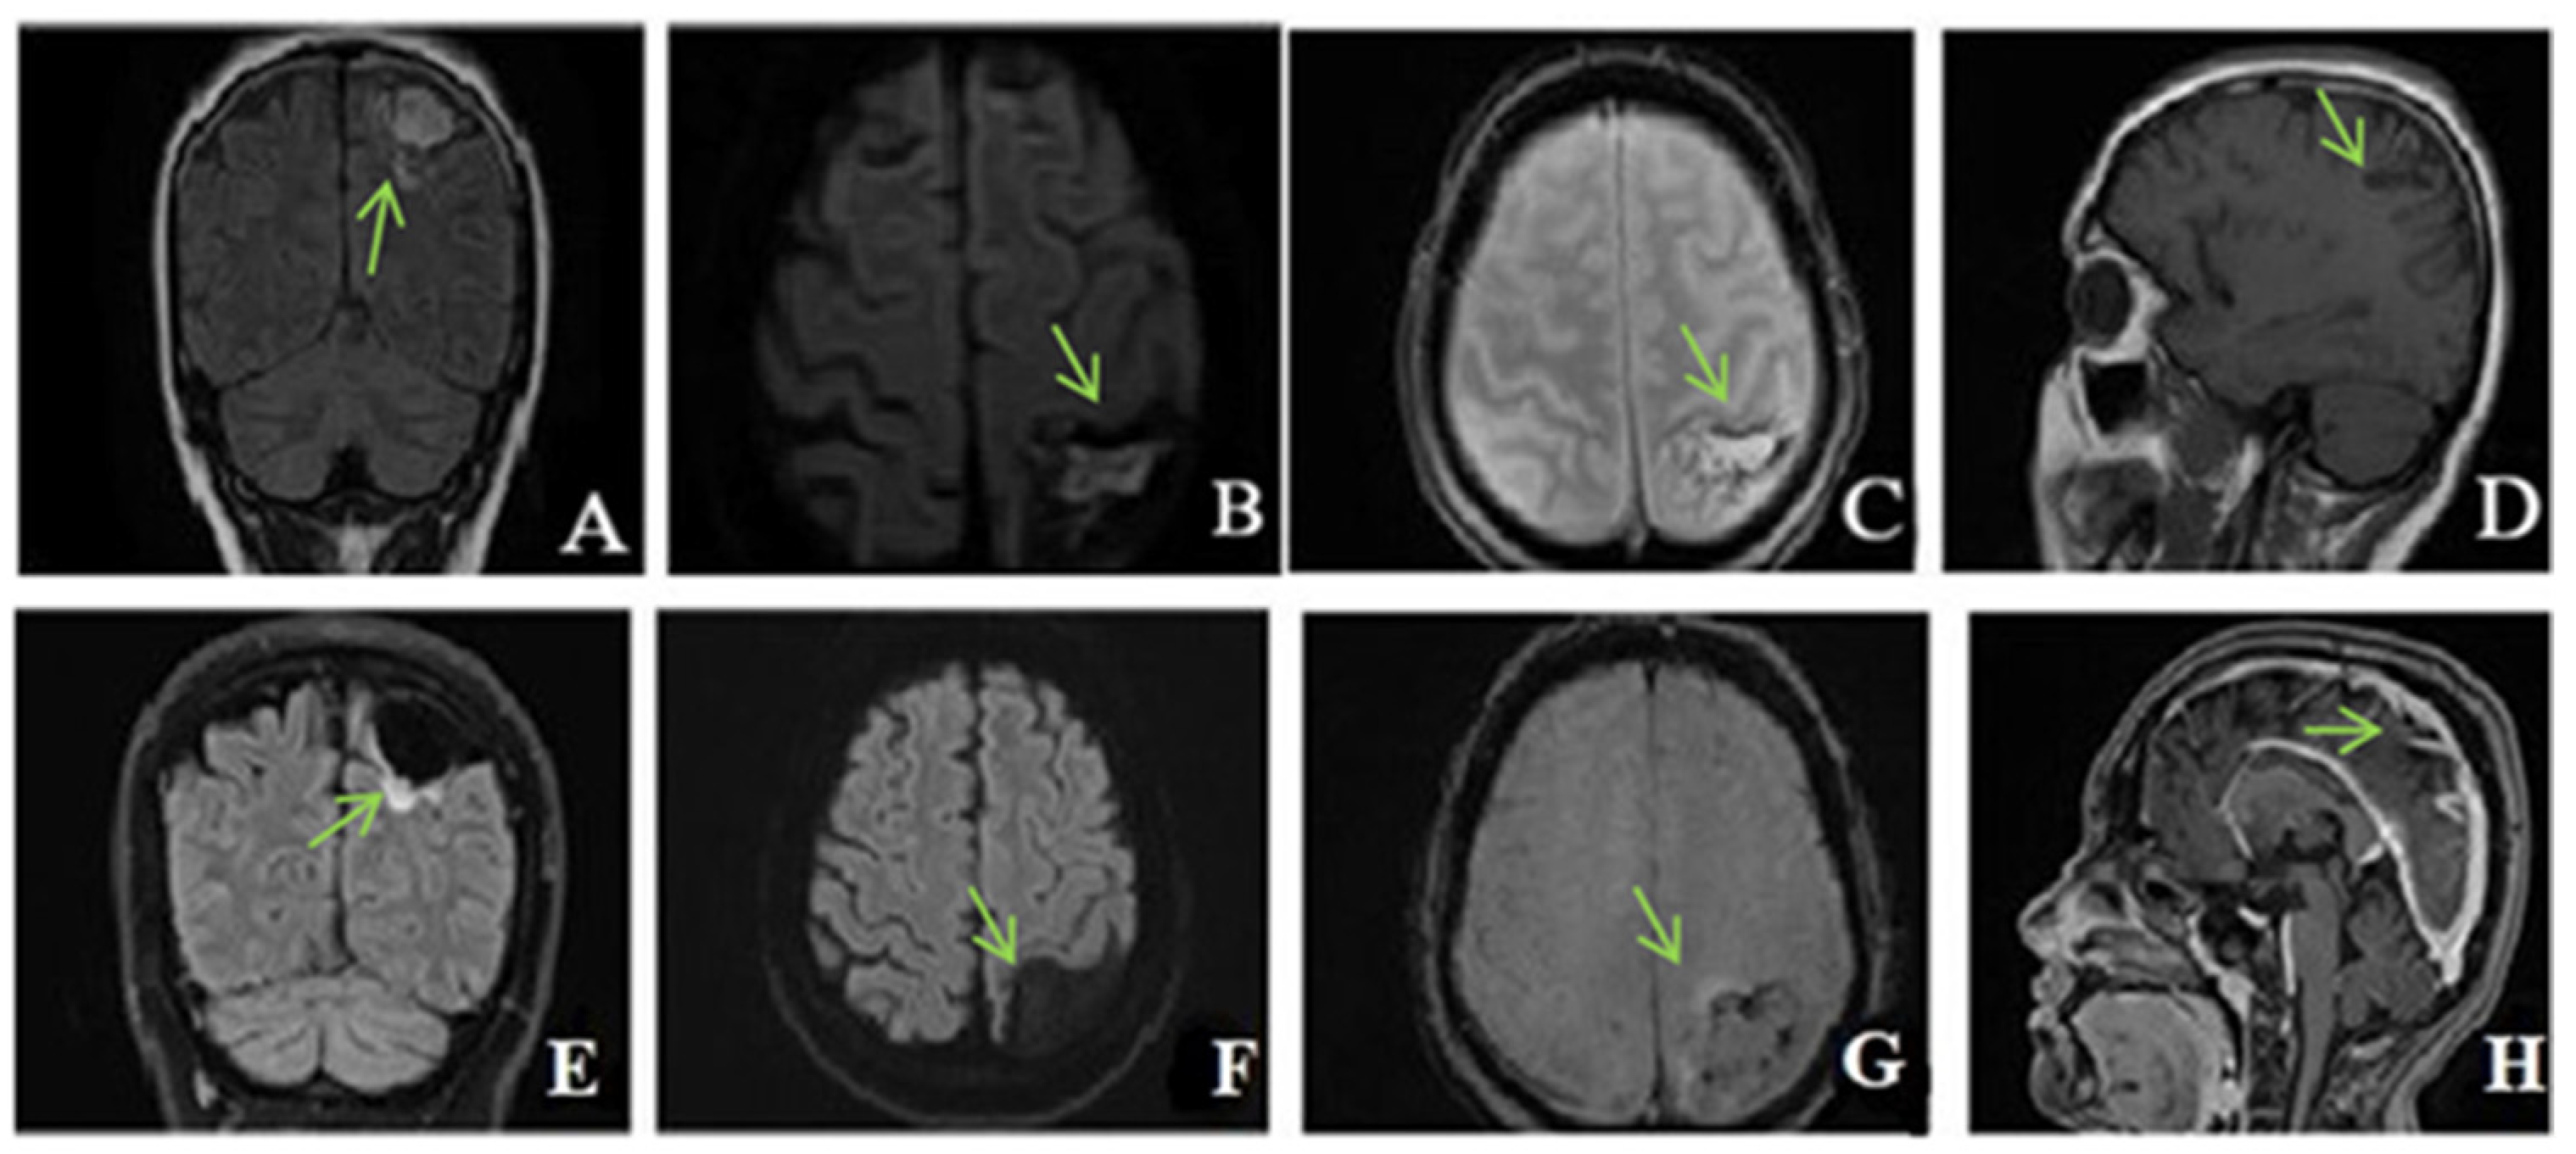

Figure 4. Unenhanced CT: (A,B)—axial, (C)—coronal, (D)—sagittal exhibits hyperdensity of the venous sinuses (sagittal superior and inferior, right sinus, transverse and sigmoid sinuses). (EH) MRI, (E)—TOF (time of fligt angiography) venous coronal; (F)—T2*hemo axial, (G)—T1 coronal after i.v. contrast, (H)—T1 sagittal after i.v. contrast, expressed extensive thrombosis of all veins.

Native head CT performed at admission (Figure 4) showed increased dimensions of sinuses, and hyperdense content in the superior longitudinal sagittal sinus, the right sinus, and, contiguously, the inferior longitudinal sinus as well as in the right transverse sinus and partially the right sigmoid sinus. Additionally, a hyperdense appearance of the cerebellar tentorium raised the suspicion of a subarachnoid hemorrhage. The hypoattenuating brain tissue is suggestive of diffuse cerebral edema.

Two days after admission, the patient underwent a contrast-enhanced brain MRI that showed extensive venous thrombosis at the level of the sagittal, transverse, and right sigmoid sinus with an increase in vascular caliber, absence of flow, and post-contrast filling defect. The association of fine bilateral high parietal subarachnoid hemorrhagic suffusions was also present, without constituted superficial parenchymal lesions. Inflammatory MRI signal changes at the level of the mastoids, frontal sinuses, and the ethmoidal cellular system were noticed, in keeping with pansinusitis.

The oral anticoagulant treatment was started with acenocoumarol, with a target INR range between 2 and 3. Clinically, the patient was stationary, without new complaints or neurological signs. Another brain MRI was performed after 9 days. Compared to the previous examination, this was showing a slightly improved appearance, with the corresponding thrombi at the level of the superior sagittal sinus being reduced.

Ten days after the discharge, he presented again to the emergency department with headache, dizziness, visual acuity disorders, and diplopia. Upon admission, an ophthalmological examination was performed, revealing bilateral papilledema. INR was within therapeutic limits (INR = 2.66). Given the symptomatology, a new angio-MRI was performed that showed improvement in thrombosis compared to the previous examination.

MRI reassessment was also performed which revealed T2 and FLAIR hypersignal, but no DWI signal of the right subcortical frontal structures—a spot of ischemic gliosis. Furthermore, parietal FLAIR and flow void signal of the transverse sinuses was present in keeping with chronic thrombosis.